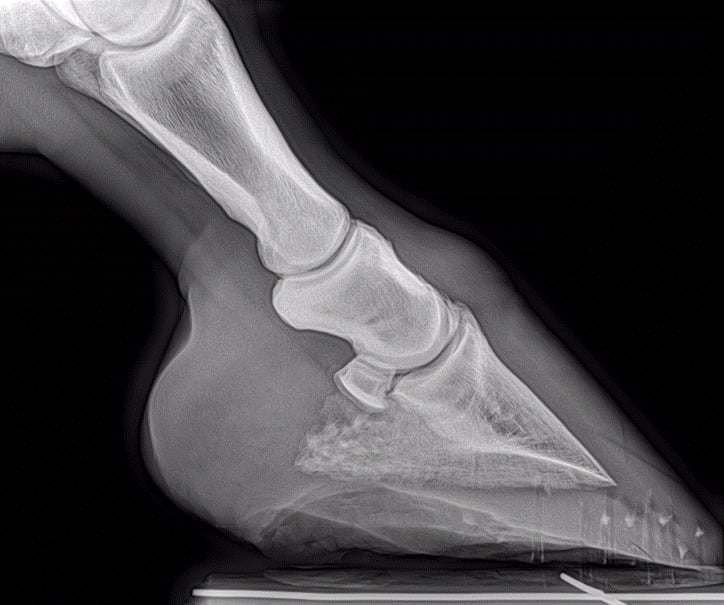

Dem Wallach wurde das Hufbein gegipst und als erstes 6 Wochen absolute Boxenruhe verordnet.

Nach zwei Wochen Boxenruhe verschlechterte sich der Zustand des Hufbeins akut. Der Wallach wurde erneut in der Pferdeklinik Neugraben untersucht und schliesslich den Bruch des Hufbeins festgestellt.

Das Hufbein wurde erneut gegipst und als ersten Therapieschritt weiterhin eine absolute Boxenruhe verordnet.